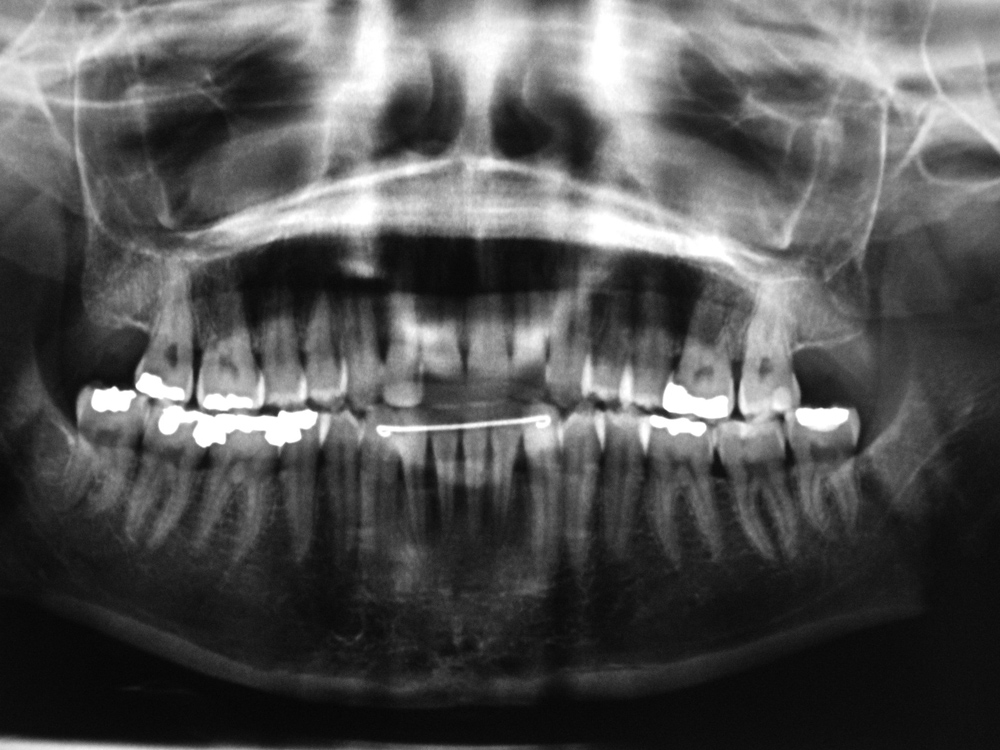

Temporomandibular prosthetic condyle implant (A); orthodontic arch bars (B); porcelain veneer dental crowns (caps) (C); fixation screws (bone screws) (D) |

Panoramic view of 38 year-old woman with a permanent (metallic) mandibular retainer. |